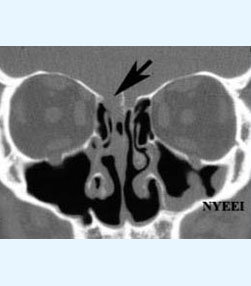

- Brain tumors - More than 1800 including pituitary, posterior fossa, intraventricular lesions, suprasellar lesions and intrinsic brain tumors